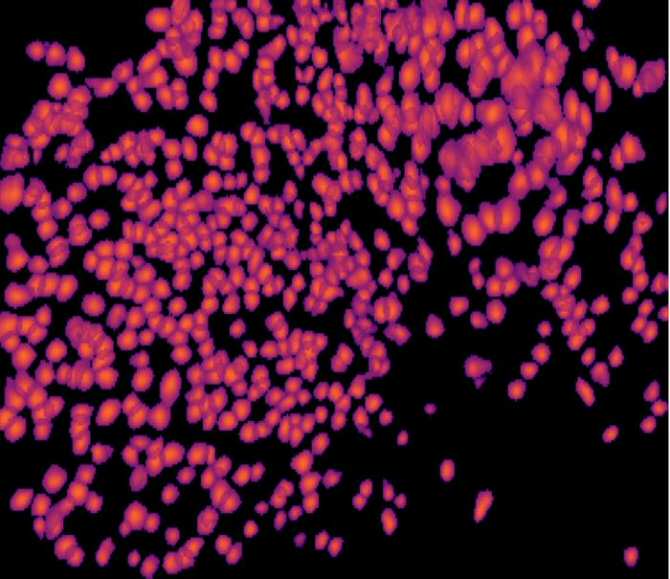

Sector del interior de un hipocampo, donde las neuronas individuales pueden identificarse visualmente y rastrearse mediante la técnica utilizada en el estudio. Cada forma resaltada corresponde a una sola neurona. (Imagen: The Brandon Lab)

En vez de depender de electrodos tradicionales, que solo pueden rastrear neuronas durante períodos cortos, los investigadores utilizaron nuevas técnicas de examen por imagen que hacen que las neuronas activas brillen. Esta tecnología permitió al equipo realizar un seguimiento de las células durante varias semanas y detectar cambios lentos que los métodos tradicionales suelen pasar por alto.